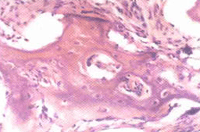

病骨大量吸收,被增生的血管組織和纖維組織代替,呈血管瘤樣表現。